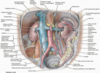

vasc of uterus

uterine A, then ovarian A

Lymphatic drainage of female reproductive organs

- ovary, uterine tube, and fundus follow the ovarian artery and drain into the paraaortic nodes/ lateral/ pre/ lumbar.

- uterine body and cervix drain into the internal and external iliac nodes

Venous drainage of prostate

prostatic venous plexus b/w true and false capsules

connect to Batson plexus (valve less)

•Veins of most of the pelvic organs are connect to Batson plexus ( except for ovaries and testis)

- how pelvic cancer can spread to the vertebral column

innervations to bladdar

vesical/prostatic plexus

PNS (s2-s4): contract detrusor, relax internal urethral sphincter

SNS: relax detrusor, constrict internal sphincter